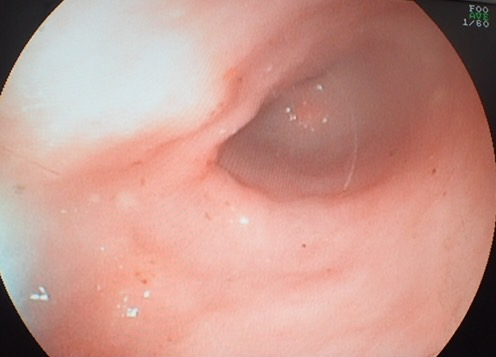

猫の慢性嘔吐に対する胃内視鏡検査(リンパ腫が疑われた症例写真)

<猫のリンパ腫が診断できることが多い>

特に猫では、腸にリンパ腫という腫瘍ができるケースが少なくありません。この病気は超音波だけでは確定できないことが多く、内視鏡による観察と生検が確定診断のカギを握ります。早期に正確な診断を行うためにも、内視鏡検査は重要な役割を担っています。

- 猫に多い腸リンパ腫